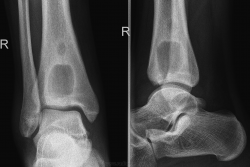

Молодой человек 18 лет поступил в стационар с ноющими периодическими болями в правом г/стопном суставе, год назад, в августе была травма(во время тренировки), по снимку без костно-травматических изменений, а вот снимок проведенный 28.06.10г.:

Вчера было проведено КТ-г/стопного сустава: